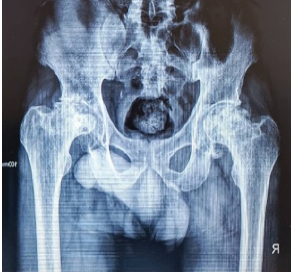

Prediction of Arterial Extravasation in Pelvic Fracture Patient with Stable Hemodynamics Using Coagulation Biomarkers: A Prospective Observational Cohort Study

Amit Kumar , Chetan Singh , Harsh Pratap Singh , Neeraj Kumar , Ashutosh Chaurasia , Anamika Bharti